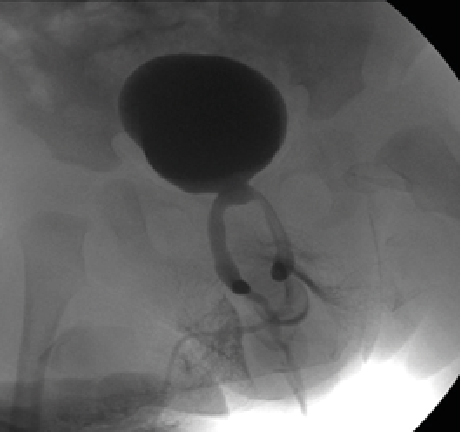

Retrograde urethrography is a very dynamic study, which must be taken into account when acquiring images, especially when sending still images, a common error is the leakage of contrast towards the skin (Figure 1) avoiding using a Foley catheter at the level of distal urethra to retain the contrast, however it can condition trauma [1]. Another common error is the ignorance of ideal projections for evaluation of the urethra (Figure 2), for example the Lauenstein projection, which is more useful for evaluating the hip. The imaging with a lack of contrast between the structures (Figure 3), which can be modified during and after the acquisition. It should be noted that on some occasions, in case of doubt, images will be taken from two different x-ray directions.

Figure 2:  AP Projections with Oblique Taking of the Penis, Avoiding Adequate Visualization of the Urethral Route